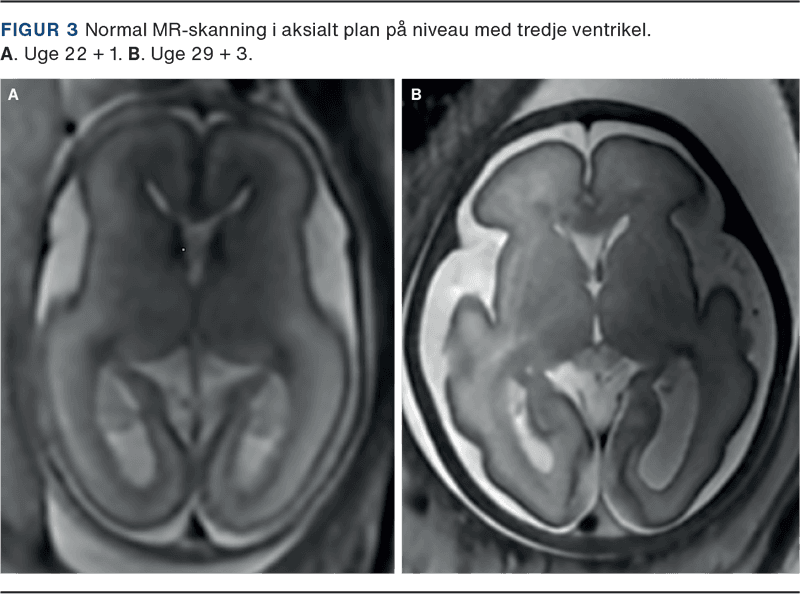

Ved UL-skanning i 2. trimester, som foretages i 18.-20. graviditetsuge, undersøges kraniet, de cerebrale strukturer, ansigt og columna/spinalkanal. Der foretages vurdering i tre planer, hvorved strukturer, som er væsentlige pejlemærker for normal udvikling af hjernen, visualiseres (Figur 3). Såfremt strukturerne ikke kan fremstilles normale, vil det medføre mistanke om abnorm udvikling af CNS. F.eks. er ventrikulomegali en hyppig markør for abnorm cerebral udvikling, manglende cavum septum pellucidium kan være et indirekte tegn på en række alvorlige midtlinjedefekter, som holoprosencefali og corpus callosum agenesi [8]. I op mod 96% af tilfælde med åben spina bifida vil der være abnorm facon af kraniet (lemon sign) og cerebellum (banana sign) [9].

Biometrier er ligeledes en væsentlig del af undersøgelsen, og der foretages ved undersøgelsen følgende mål: hovedomfang, diameter af lateralventriklerne og cerebellum. Hovedets vækst er betinget af vækst af hjernen og er dermed en markør for normal udvikling af hjernen. Diagnosen mikrocefali kan dog oftest først stilles sent i 2. trimester eller i 3. trimester

Der foretages ved den neurosonografiske undersøgelse skanning i tre transverselle, fire koronale og tre sagittale planer [10, 11]. I det sagittale plan er det bl.a. muligt at fremstille corpus callosum og vurdere størrelse og morfologi på vermis cerebelli og hjernestammen. I koronalplanet er det under optimale omstændigheder muligt at visualisere den laminære opbygning af parenkymet. Oftest er der dog behov for MR-skanning for at vurdere udviklingen af parenkymet.

En generel vurdering af cortex cerebri og de begyndende sulci, fissurer og gyri er ligeledes en del af den neurosonografiske undersøgelse. Tidspunkt for dannelsen af de forskellige sulci og fissurer er i den normale udvikling meget præcis og derfor gode markører for hjernens udvikling [12].